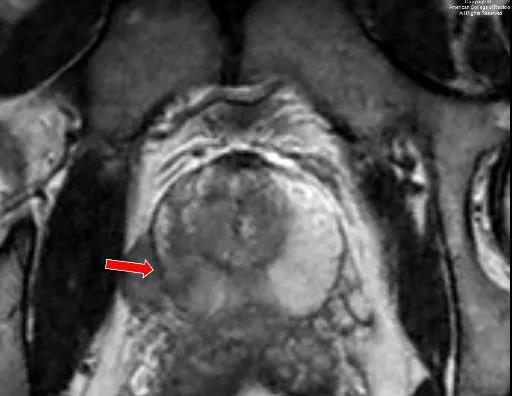

4.核磁共振(MRI)检查:

MRI检查可以显示前列腺薄膜完整性,肿瘤是否侵犯前列腺周围组织和器官,也可以盆腔淋巴结受侵犯情况及骨转移病灶。在临床分期上具有重要作用。